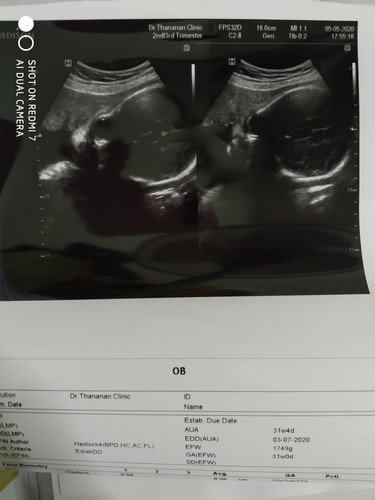

ท้องได้29+2ค่ะทำไมดูในภาพเหมือหัวเด็กดูโต

เลยอยากถามคูณแม่ๆที่มีประสบการณ์ค่ะ คูณหมอก็บอกปกติทุกอย่างค่ะแต่ทำไมดูในภาพเหมือนหัวเด็กดูโตหรือเป็นเพราะคูณหมอถ่ายให้ดูใกล้ๆเลยดูหัวโต?คูณแม่ๆพอจะทราบมั้ยค่ะ?

ไม่ต้องกังวลนะคะแม่ หมอคอนเฟิร์มแล้วว่าปกติ ของเราซาวด์มาก็ดูหัวโตๆเหมือนกันค่ะ ดูจาก HC